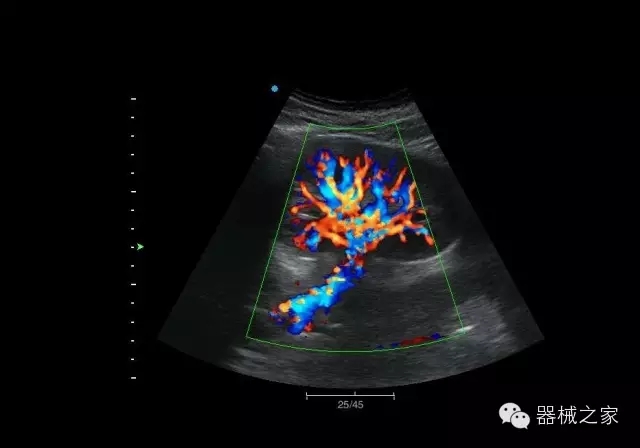

經(jīng)典產(chǎn)品:Apogee 1000

臨床圖片賞析

結(jié)甲

腎臟血流

肝血管瘤

產(chǎn)品特點(diǎn)

·屏幕可左右90度旋轉(zhuǎn);

·雙模操控;

·兩用提手;

·雙鋰電池;

·超輕機(jī)身;

·15寸高亮高清醫(yī)學(xué)顯示器;

·衛(wèi)星布局操控面板;

·一體化剪切板;

·多功能導(dǎo)航鍵;

“宏云”平臺

·采用移植自高端臺式彩超的“宏云”平臺技術(shù),使系統(tǒng)具有更優(yōu)秀的圖像效果;

人性化的設(shè)計(jì)

·內(nèi)置電池,輕巧的外觀設(shè)計(jì)以及臨床功能、軟硬件設(shè)計(jì)的人性化設(shè)計(jì),使系統(tǒng)在臨床多科室移動診查中,均從容應(yīng)對;

Fusion THI二代融合諧波成像

·在不同諧波頻率段獲得的信息進(jìn)行實(shí)時融合,既能獲得諧波圖像分辨率又能提高圖像的穿透力,降低圖像噪音;

XBeam多域復(fù)合成像

·通過頻域和空域角度進(jìn)行復(fù)合的圖像處理,能有效消除由于圖像離散化和圖像衰減引起的空間分辨率下降的不利影響,彌補(bǔ)原有圖像空間分辨率的不足,獲得更加清晰的圖像;

CFDA注冊證編號

·粵食藥監(jiān)械(準(zhǔn))字2014第2231316號